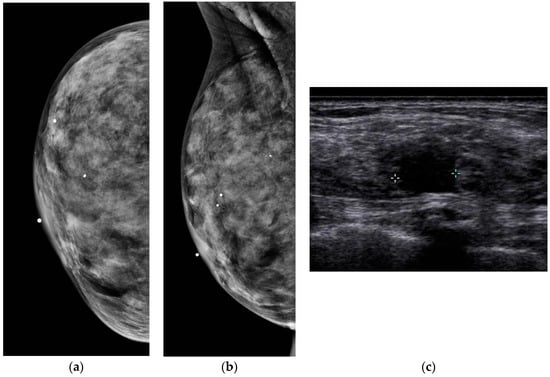

Figure 3.

A 53-year-old woman with dense breasts and a palpable abnormality presents for evaluation. (a,b) Implant displaced CC and ML digital mammograms fail to reveal a mass (triangle denotes palpable abnormality). (c) High resolution handheld ultrasound easily depicts a 0.9 cm spiculated mass due to invasive ductal carcinoma.